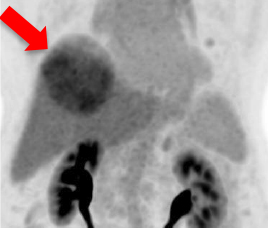

- 3-month post-treatment dual tracer PET/CT

- Liver tumor metabolism and size are reduced

- AFP drops to 1206 ng/ml

C-11 Acetate F-18 FDG